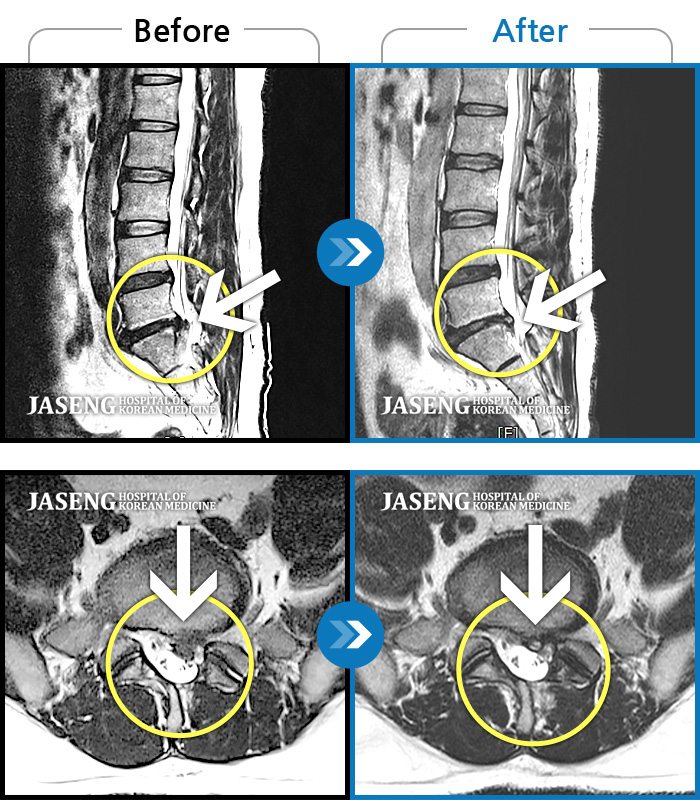

40대 초반 여성 환자인데요,, 처음 선생님 뵈었을 때에 1번,4,5번허리디스크 증상도 증상이지만,

본인 나이에 비해서 10~15년정도 퇴행이 많이 되어있어서 전체적으로 관리가 많이 필요하다고 설명해주셨구요,,

그당시 원장님진료실에서 보았던 저의 엠알아이사진이 아직도 생생히 기억이 납니다 ^^

뼈부분의 색이 왜저렇게 검냐고 여쭈어 보았더니, 말씀주신데로 "퇴행이"많이 되어서 그렇다고 설명해주시면서,,